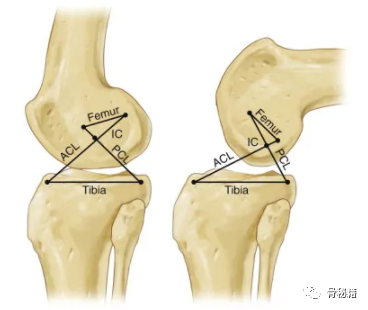

十字连杆模型。

该模型包括两个交叉条,代表前交叉韧带和后交叉韧带(ACL、PCL)。

剩下的两个条形代表韧带的胫骨和股骨附着点。

IC,关节旋转的瞬时中心。